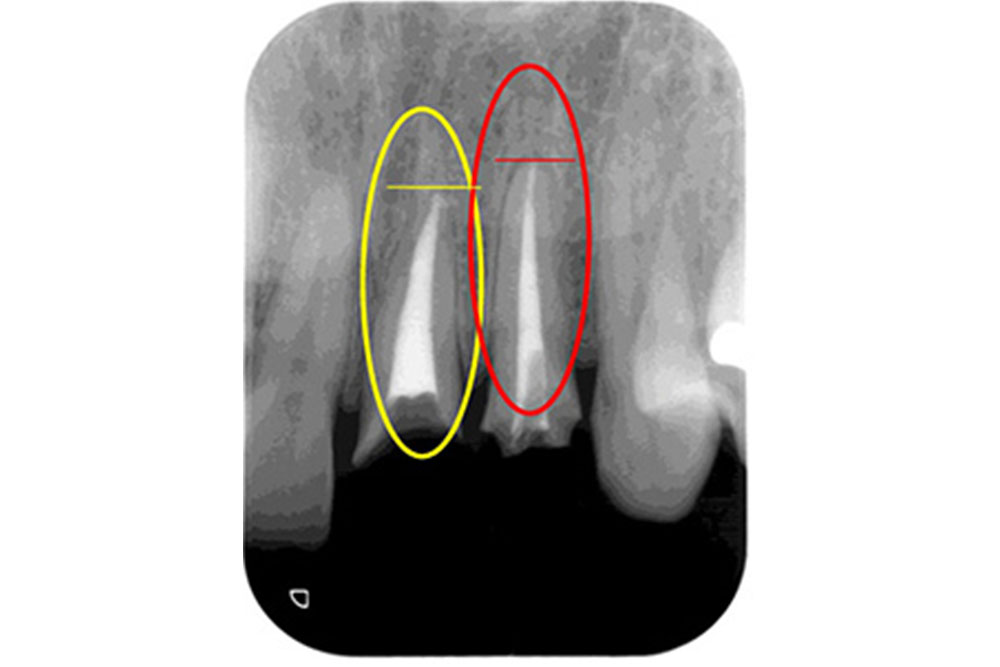

▲他の歯科医院での根の治療

▲当院でやり直した治療

他の医院で根の治療を行った患者様が「痛みを感じる」と来院された例があります。診察すると、治療を受けた部分は歯の先端まで白い充填物が入っておらず隙間だらけで、先端に膿が溜まっていました。そこで当院は根の先端まで隙間なく白い充填物を入れて痛みを消失させました。ここで可能であれば、歯を長期使用するためにしっかりした被せ物をします。被せ物は充填物同様、その歯の予後を左右する大事な要因となります。